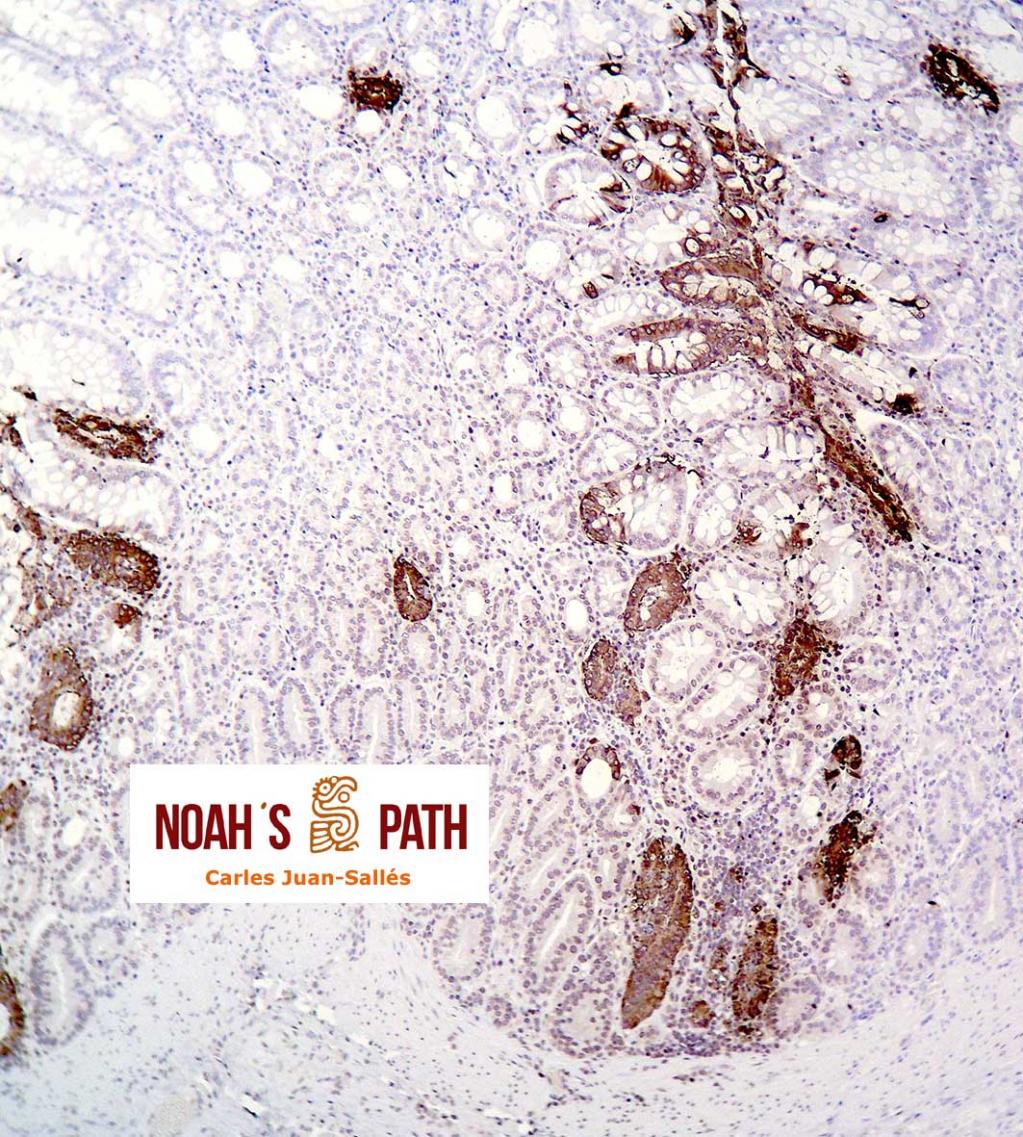

Estudio clínico-patológico e inmunohistoquímico de un brote de mortalidad en elands juveniles debido a infección intestinal por coronavirus en colaboración con Santiago Borragán del Parque de la Naturaleza de Cabárceno y Pepe Ramos de la University of Purdue.